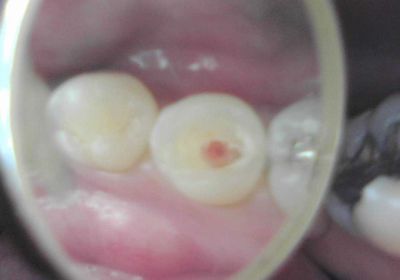

■女性:他院で左上の虫歯治療をしていたが、神経が出てきたので抜髄と言われた。何とか神経を残せないか

左上6番、セメントが詰めてある。冷水痛(+)、自発痛(+-)、打診痛(+)

うーん、こりゃダメなんじゃ・・・

セメント除去したら、ドワァと出血。こ、こりゃ直接覆髄じゃダメ多分。

レーザー当てたりヘモデントで止血を試みたがダメでしたので、

生活歯髄切断法に切り替えました。